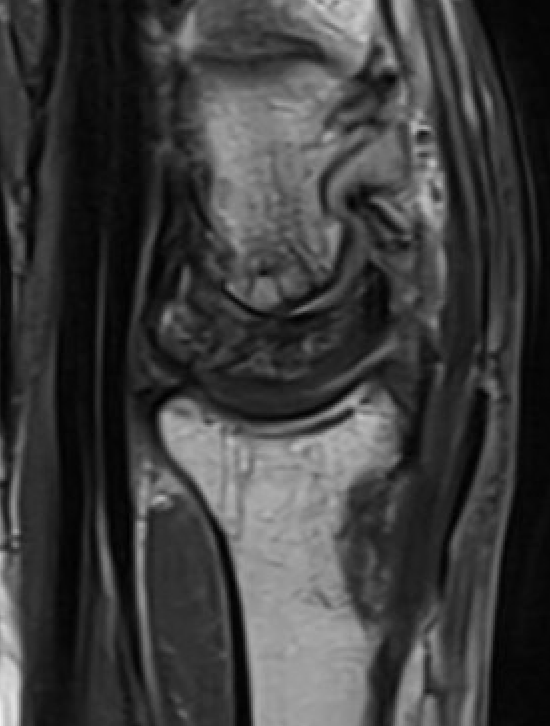

Lunate precollapse

CT demonstrating lunate fragmentation and collapse